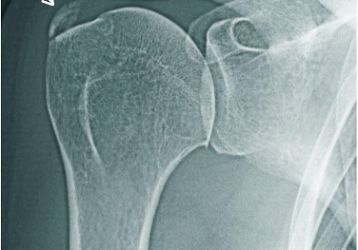

Артроз плечевого сустава — полное описание заболевания, симптомы и эффективные методы лечения

Артроз плечевого сустава: симптомы и лечение. Полное описание заболевания, причины возникновения и диагностика. Лекарства при артрозе плечевого сустава.